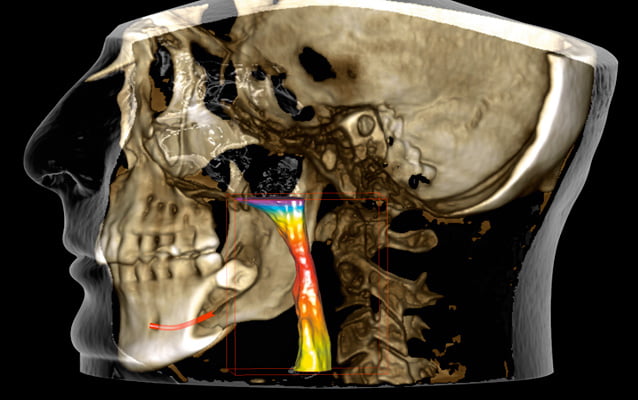

Protokół Planmeca Ultra Low Dose okazał się idealny do szerokiego zakresu zastosowań klinicznych, od ortodoncji do planowania implantów, chirurgii szczękowej oraz badań dróg oddechowych i zatok.

Planmeca Ultra Low Dose może być stosowany ze wszystkimi rozmiarami wokseli i wszystkimi trybami obrazowania, od najmniejszego rozmiaru woksela do największego pola widzenia (FOV). Ten protokół obrazowania jest idealny, gdy wymagane są szczegółowe informacje anatomiczne przy bardzo niskich dawkach promieniowania.

W pełni innowacyjny i naukowo zatwierdzony protokół obrazowania oparty na inteligentnych algorytmach 3D znacznie zmniejsza dawkę dla pacjenta bez pogorszenia jakości obrazu, zapewniając klinicystom na całym świecie możliwość skutecznego stosowania ALADY (minimalnej akceptowalnej diagnozy). Dążymy do tego, aby mieli taką możliwość. Stosowanie i skuteczność Donk Eye zostało naukowo zbadane i udowodnione w różnych badaniach.

Wysoka rozdzielczość i duża dawka nie zawsze są niezbędnymi standardami i często mniej znaczy więcej. Na przykład obrazowanie ultraniskodawkowe Planmeca jest niezbędne do uwidocznienia kanału nerwu żuchwowego przy planowaniu implantów i ekstrakcji zębów mądrości. Wszystko to można osiągnąć przy wyjątkowo niskich dawkach.